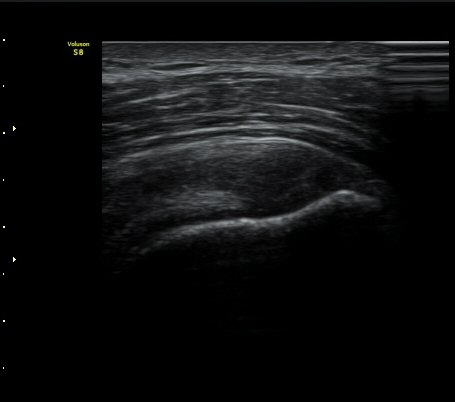

±Ø»ó°Ç Ⱦ´Ü¸é°Ë»ç½Ã ±Ø»ó°Ç ÀϺΠÀú¿¡ÄÚ ºÎÁ¾°ú ¹Ì¼¼ÇÑ °Ç ¿¬°á¼º ¼Ò½ÇÀÌ °üÂûµÊ(±×¸² 4, 5).

±×¸² 4)¿¡¼­ °üÀý¿¬°ñ°æ°è¸é ¡ÈÄ(articular interface sign)°¡ °üÂûµÊ.